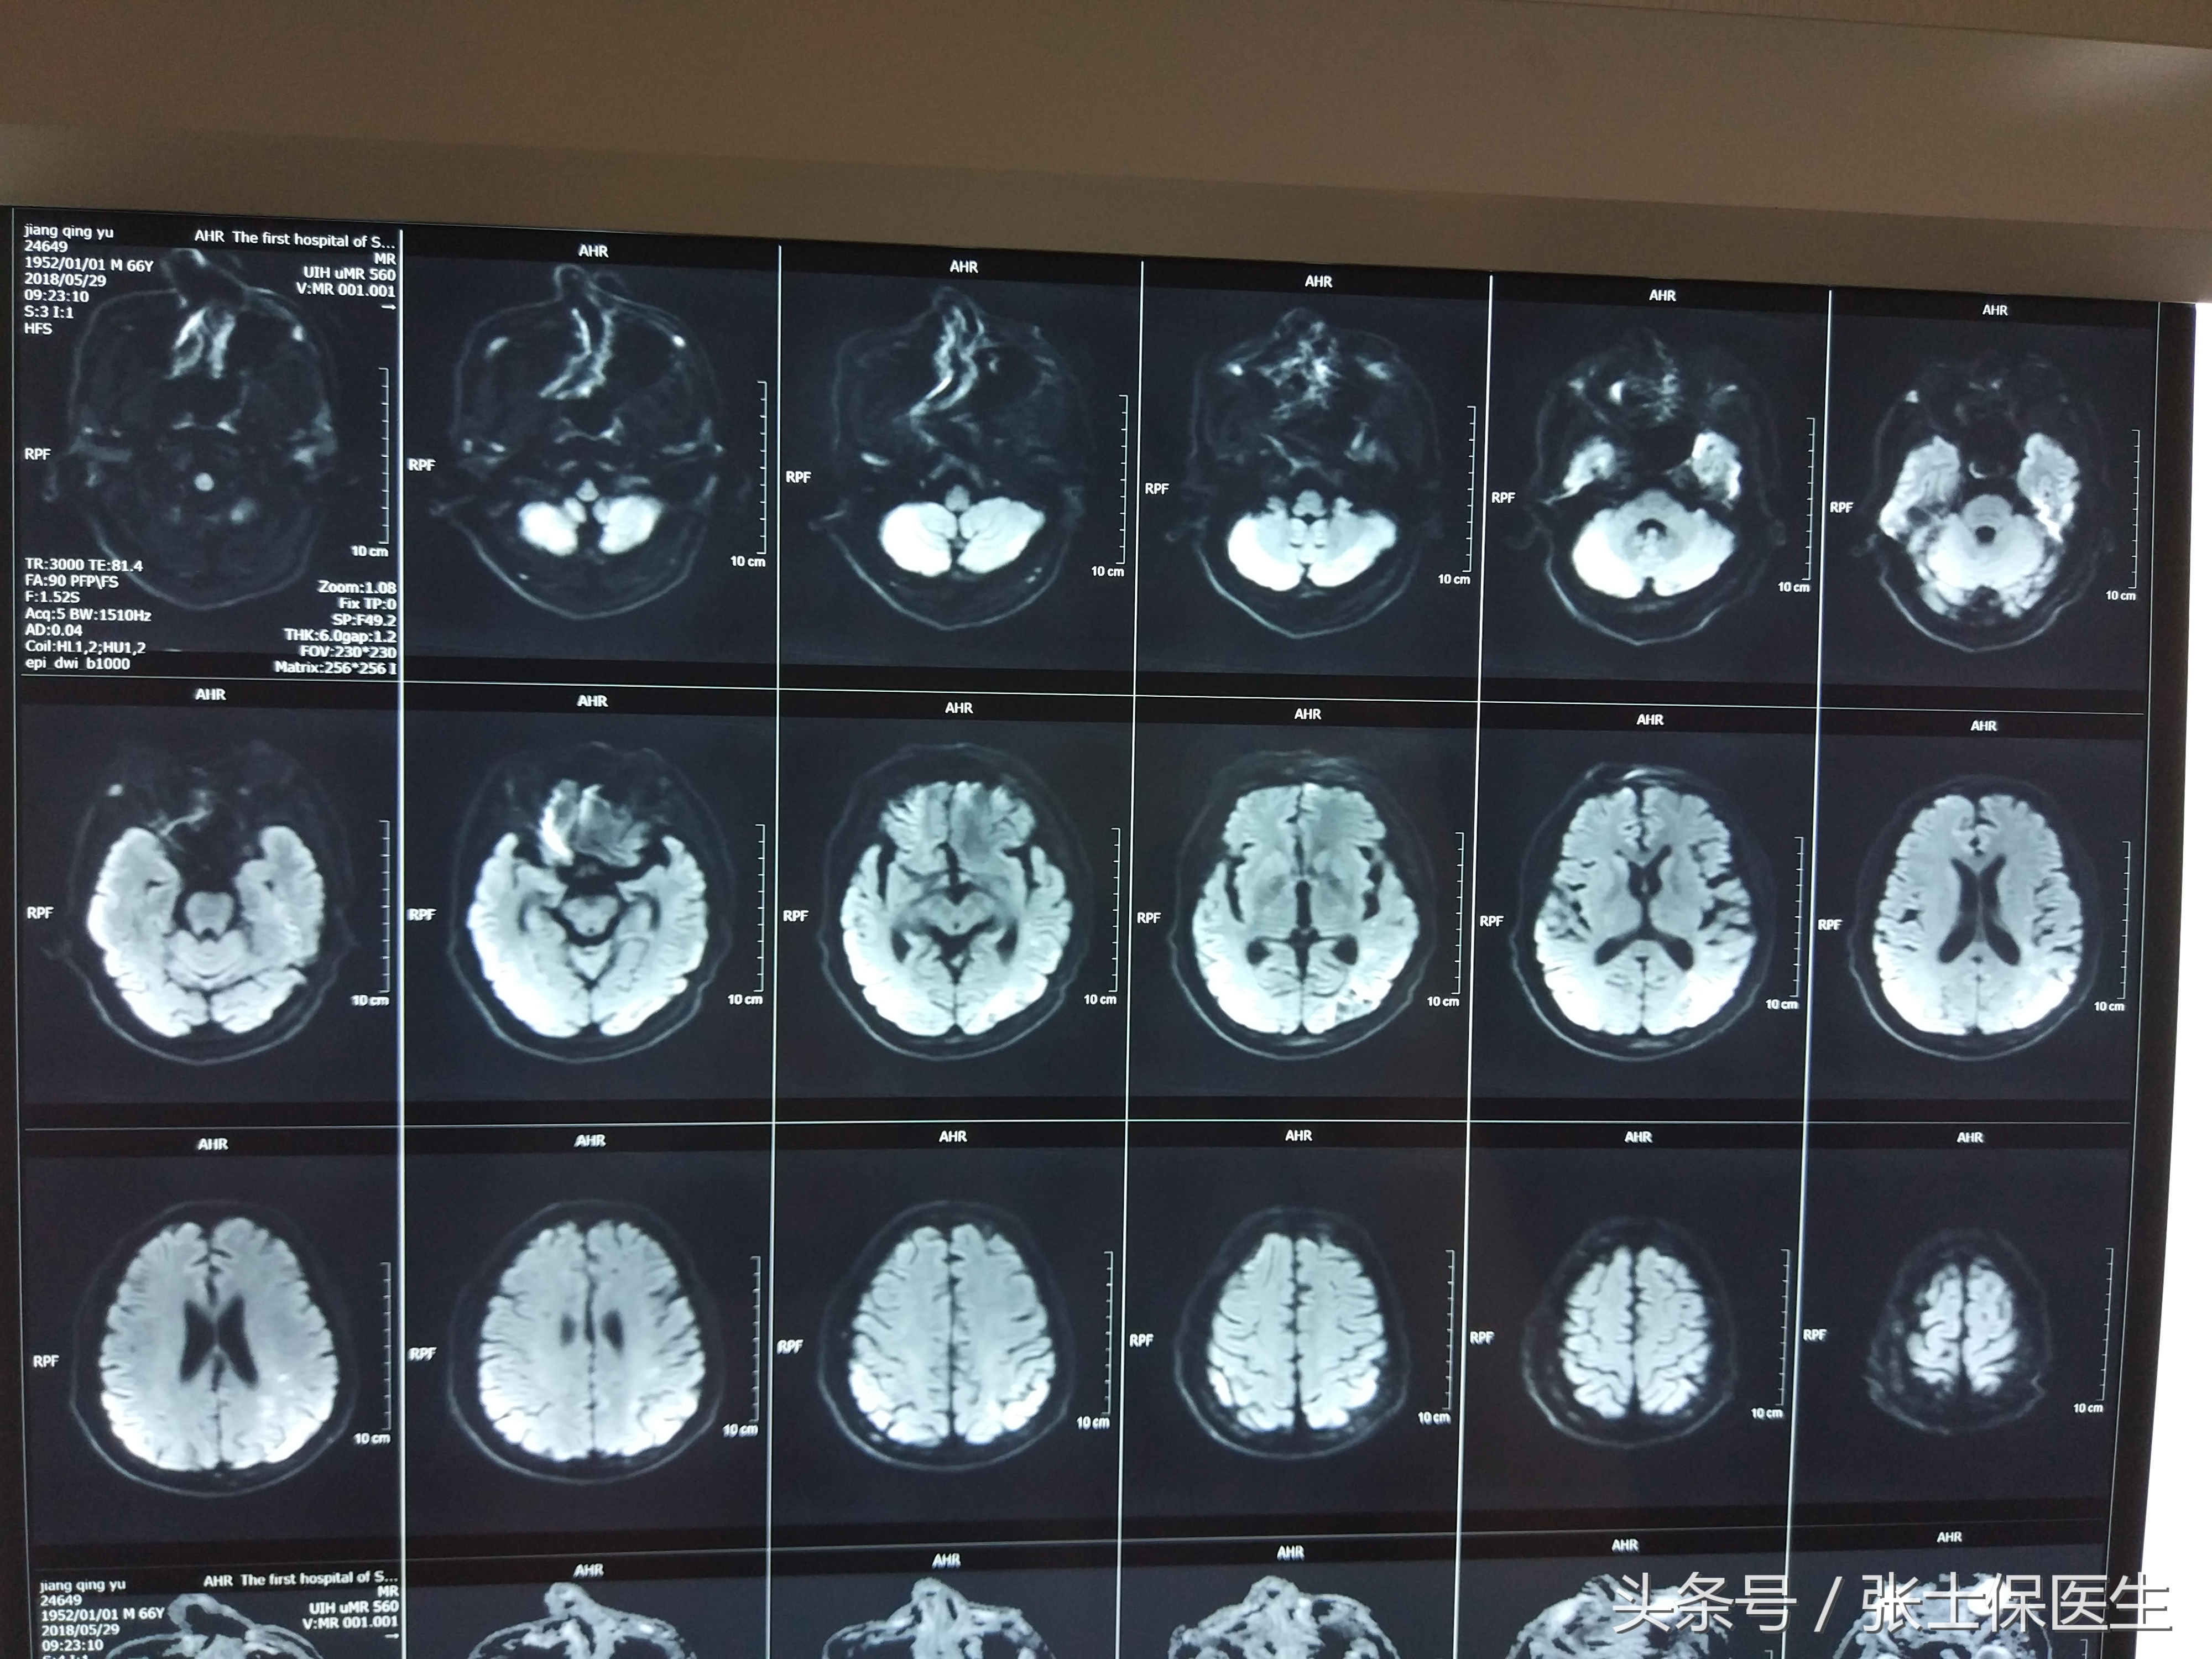

​脑梗死是指各种原因引起的脑部血液供应障碍造成局部脑组织发生不可逆性损害,导致脑组织缺血、缺氧性坏死。脑梗死患者救治中以下环节很重要。

目前,溶栓治疗——脑梗死最有效的药物治疗方法!但溶栓是有时间窗的:静脉溶栓阿替普酶时间为4.5小时,尿激酶溶栓的时间为6小时。

由以上介绍看到时间对于脑梗死患者多么重要!超早期溶栓治疗及时恢复脑组织血流和脑代谢以抢救梗死周围半暗带(没完全死亡的脑细胞),减轻神经损伤!如果静脉溶栓不理想,医生根据你的病情还可以采取桥接治疗,桥接治疗就是血管内介入治疗,采用动脉溶栓以及机械取栓相结合,能够有效的开通堵塞的血管,来患者缓解疾病症状。但对于这些有效治疗方法的选择一切都是以时间为基础的,记住:时间就是大脑!